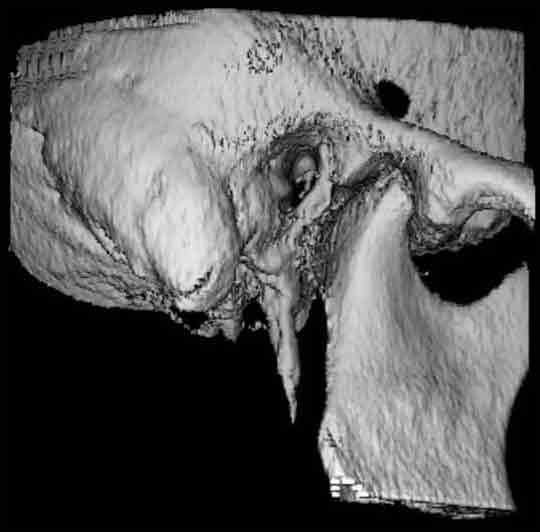

Hier verläuft der Nervkanal direkt durch den Weisheitszahn. Dieser Befund kann nur durch die zweite Ebene gesichert werden. Das DVT erlaubt eine sichere Diagnostik und hilft, sicher zu entscheiden.